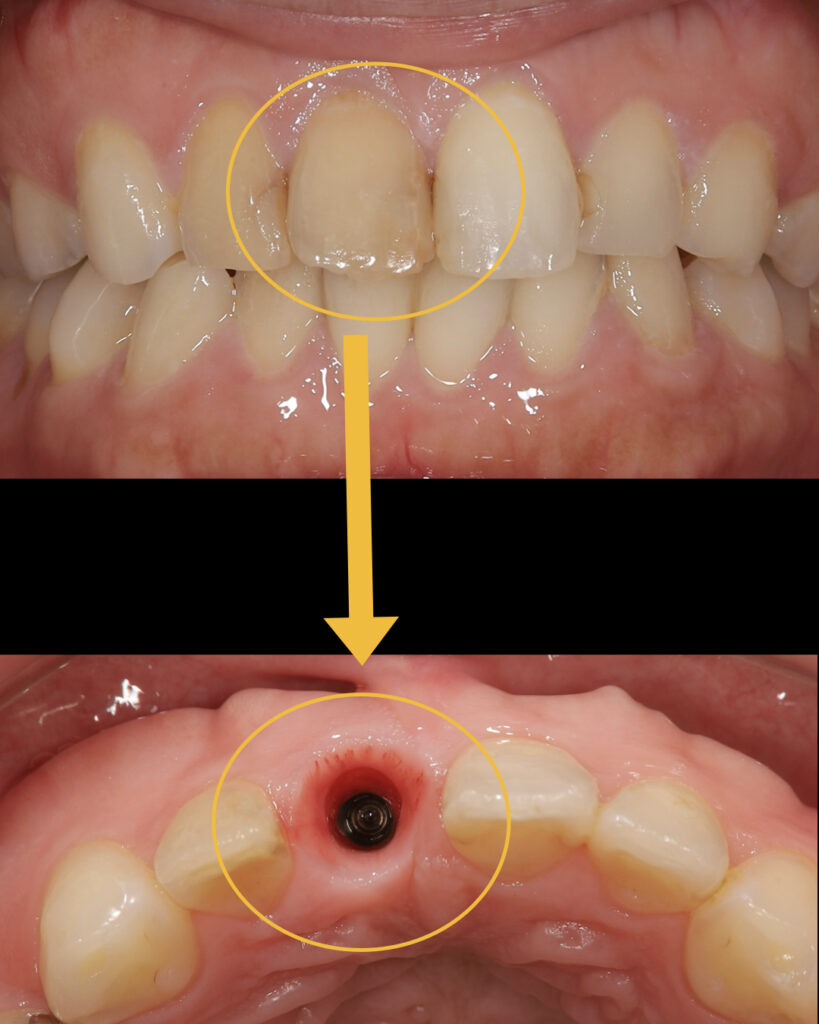

患者様は矯正治療を希望され当院を来院されました。右上の前歯が変色しており、お聞きすると昔小学生の頃にぶつけてしまったということでした。資料採りを行い診査診断を行ったところ、根先が吸収されており短くなっていました。

幼少時代に前歯をぶつけてしまい、神経が死んでしまい根が吸収される方はよくいます。ただし、この歯を矯正治療で動かすと抜け落ちてしまう可能性があり、さらに、この歯は長期的予後も悪いことを説明すると、矯正を含めたインプラント治療を希望されました。

歯を抜くこと自体は容易であり、インプラント手術も20分程度で終了しました。歯を抜くと同時にインプラント埋入を行う抜歯即時インプラントを行い、痛みもほとんどなく患者様は大変喜ばれていました。

インプラントが生着すると、仮歯を装着します。審美領域のインプラント治療において

仮歯の調整が非常に重要になります。この段階で歯茎の高さや形を調整します。

左右均等に仮歯を調整し、歯肉ラインや形態など審美的に整えた後、その情報を技工所に正確に伝え最終的なセラミックに作製します。